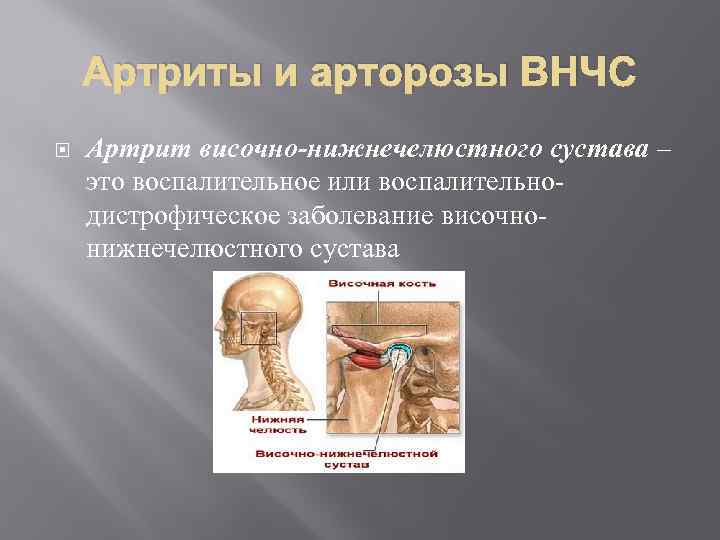

Дистрофические заболевания внчс презентация - 89 фото